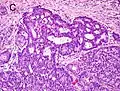

Gleason pattern 4. H&E stain.

Gleason 4

Gleason pattern 4 glands are no longer single/separated glands like those seen in patterns 1-3. They look fused together, difficult to distinguish, with rare lumen formation vs Gleason 1-3 which usually all have open lumens (spaces) within the glands, or can be cribriform-(resembling the cribriform plate/similar to a sieve: an item with many perforations). Fused glands are chains, nests, or groups of glands that are no longer entirely separated by stroma-(connective tissue that normally separates individual glands in this case). Fused glands contain occasional stroma giving the appearance of "partial" separation of the glands. Due to this partial separation, fused glands sometimes have a scalloped (think looking at a slice of bread with bite taken out of it) appearance at their edges.[4][7]